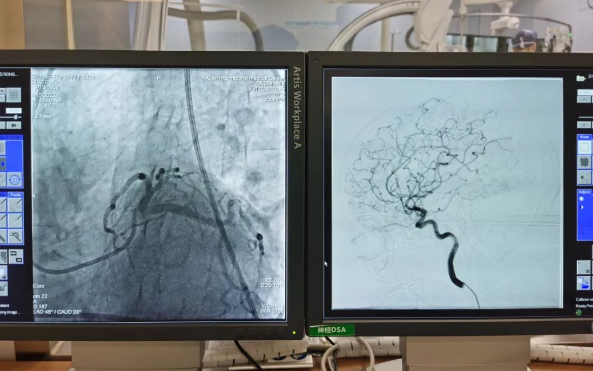

術(shù)前準(zhǔn)備就緒后,心內(nèi)二病區(qū)曾廣偉主任、高釗副主任醫(yī)師、神外科陸丹副主任醫(yī)師共同為患者行腦血管造影術(shù) 冠狀造影術(shù)。術(shù)后,朱奶奶恢復(fù)良好。

陸丹副主任醫(yī)師介紹,由于腦血管疾病和心血管疾病有著共同的病理變化基礎(chǔ)——?jiǎng)用}粥樣硬化,臨床中,兩類疾病交叉存在的情況十分多見?!靶哪X同治”的模式不僅能讓患者獲得較好治療,還能夠降低患者就醫(yī)的時(shí)間成本和經(jīng)濟(jì)成本。